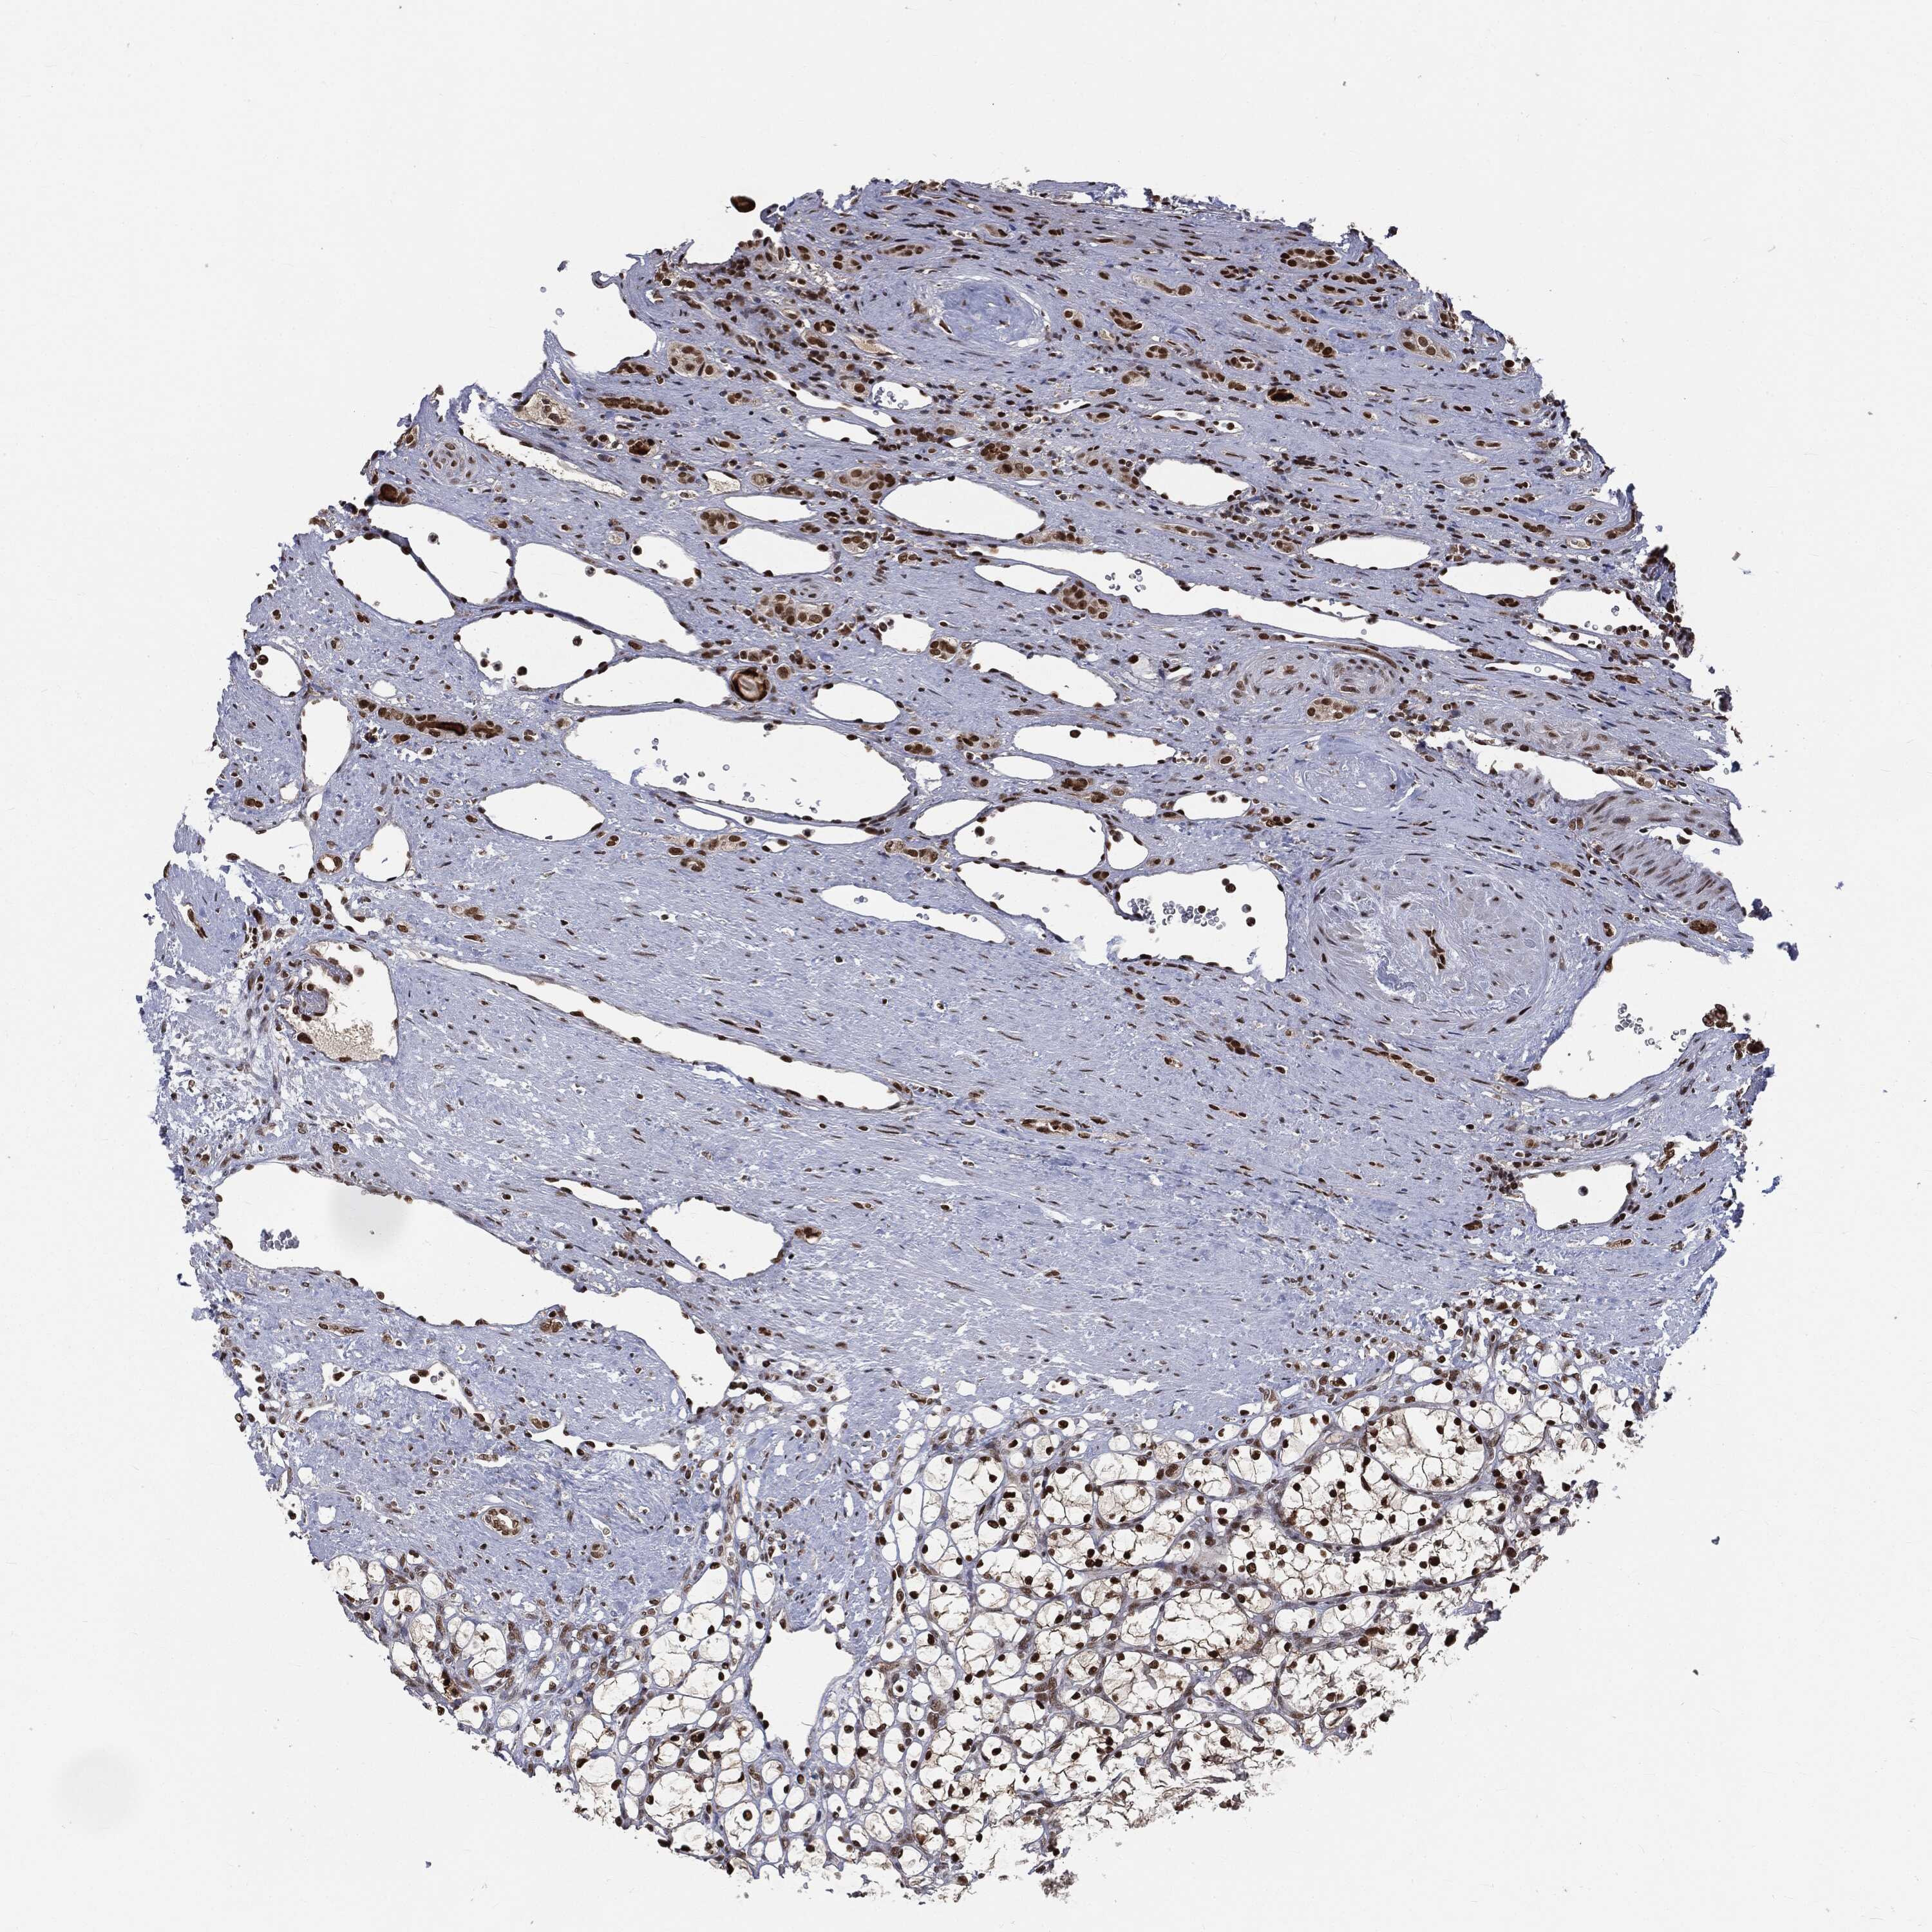

KIDNEY CHROMOPHOBE (TCGA) - Interactive survival scatter ploti

The Survival Scatter plot shows the clinical status (i.e. dead or alive) for all individuals in the patient cohort, based on the same data that underlies the corresponding Kaplan-Meier plots. Patients that are alive at last time for follow-up are shown in blue and patients who have died during the study are shown in red.

The x-axis shows the expression levels (FPKM) of the investigated gene in the tumor tissue at the time of diagnosis. The y-axis shows the follow-up time after diagnosis (years). Both axes are complimented with kernel density curves demonstrating the data density over the axes. The top density plot shows the expression levels (FPKM) distribution among dead (red) and alive patients (blue). The right density plot shows the data density of the survived years of dead patients with high and low expression levels respectively, stratified using the cutoff indicated by the vertical dashed line through the Survival Scatter plot. This cutoff is automatically defined based on the FPKM cutoff that minimizes the p-score. The cutoff can be changed by dragging the vertical line or by entering a cutoff value in the square labeled "Current cut-off".

Under the Survival Scatter plot the p-score landscape (black curve; left axis) is shown together with dead median separation (red curve; right axis). Dead median separation is the difference in median mRNA expression between patients who have died with high and low expression, respectively. It is calculated as follows: median FPKM expression of dead patients with high expression - median FPKM expression of dead patients with low expression. This is intended to aid the user in visually exploring custom cutoffs and the associated p-scores and dead median separation.

Individual patient data is displayed and can be filtered by clicking on one or more of the category buttons on the top of the page. Categories describing expression level and patient information include: high, low, alive, dead, female, male and tumor stages. The scale of the x-axis can be toggled between linear and log-scale by clicking on the "x log" button. Mouse-over function shows TCGA ID, patient information and mRNA expression (FPKM) for each patient.

& Survival analysisi

Kaplan-Meier plots summarize results from analysis of correlation between mRNA expression level and patient survival. Patients were divided based on level of expression into one of the two groups "low" (under cut off) or "high" (over cut off). X-axis shows time for survival (years) and y-axis shows the probability of survival, where 1.0 corresponds to 100 percent.

DPH2 is not prognostic in Kidney Chromophobe (TCGA)

Best expression cut offi

Based on the FPKM value of each gene, patients were classified into two groups and association between prognosis (survival) and gene expression (FPKM) was examined. The best expression cut-off refers the FPKM value that yields maximal difference with regard to survival between the two groups at the lowest log-rank P-value. Best expression cut-off was selected based on survival analysis .

When clicking on this number, the vertical dashed line indicating cut-off, the interactive survival plot, and the Kaplan-Meier curve will be adjusted to show results based on the best expression cut-off.

: 10.17

Median expressioni

Median expression refers to the median FPKM value calculated based on the gene expression (FPKM) data from all patients in this dataset. When clicking on this number, the vertical dashed line indicating cut-off, the interactive survival plot, and the Kaplan-Meier curve will be adjusted to show results based on the median expression.

: N/A

Median follow up timei

Median follow up time refers to the median time (years) after diagnosis with this type of cancer, based on clinical data from all patients in this dataset.

P scorei

Log-rank P value for Kaplan-Meier plot showing results from analysis of correlation between mRNA expression level and patient survival.

N/A

5-year survival highi

5-year survival for patients with higher expression than the expression cutoff.

For melanoma and glioma, 3-year survival is shown.

5-year survival lowi

5-year survival for patients with lower expression than the expression cutoff.

TCGA RNA samplesi

RNA-seq data is reported as average FPKM (number Fragments Per Kilobase of exon per Million reads), generated by the The Cancer Genome Atlas (TCGA) .

Normal distribution across the dataset is visualized with box plots, shown as median and 25th and 75th percentiles. Points are displayed as outliers if they are above or below 1.5 times the interquartile range. FPKM values of the individual samples are presented next to the box plot.

Average pTPM 8.3

Number of samples 64